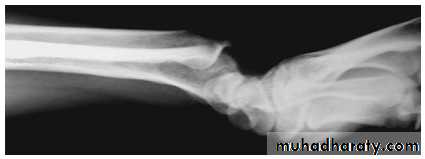

Madelung deformity

Forward curvature of the lower radius and backward subluxation of the lower ulna.

Cause: congenital or post-traumatic.

If symptomatic treated by radial osteotomy.